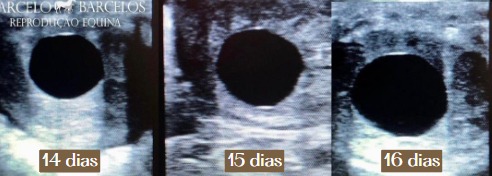

11 – 16 dias Crescimento da Vesícula Embrionária

A vesícula embrionária pode ser observada a partir do 10º dia pós-ovulação. Ela apresenta formato esférico e cresce rapidamente.

Aos 14 dias, seu diâmetro pode variar entre 8-12 mm, e até os 16 dias, pode atingir 18-20 mm. Durante esse período, o embrião realiza uma migração uterina ativa, essencial para o reconhecimento materno da gestação (em equinos) e a manutenção do corpo lúteo.

A partir do 11º-12º dia, pode-se visualizar via ultrassom uma estrutura anecóica (preta) no útero, que representa a vesícula embrionária cheia de fluido.